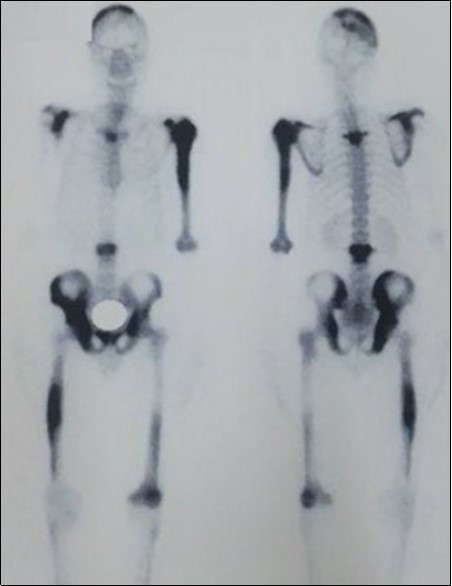

We report the case of an asymptomatic 49 years old male patient, in which a routine check objectified a biological cholestasis (gammagmutamytransferase = 2-3N and ALP = 5-6 N without hyperbilirubinemia or cytolysis). Nos past medical facts were noted. Abdominal ultrasound, viral markers and antibodies measurement (Ac Anti-nuclear, anti-Mitochondrial, anti-LKM1, Anti-cytoplasmic) were normal. Magnetic resonance choalngiopancreatography objectified multiple biliary strictures and parietal irregularities evocative of SC (Figure 1). Colonoscopy showed no associated inflammatory bowel disease. Patient received high doses of ursodeoxycholic acid (20mg/kg) for the SC with partial improvement of liver function but persistence of a marked rise in ALP level. In order to better characterize the nature of ALP, a dosage of ALP isoenzymes was performed and objectified a predominant bone fraction (83%), while liver fractions H1 and H2 were respectively of 12% and 4%. X rays objectified bone condensations with a fibrillar appearance and bone hypertrophy suggestive of PD (Figure 2). A bone scan made for lesions mapping showed a multifocal PD (Figure 3). The patient was treated by bisphosphonates (injections of zoledronic acid), which was associated with a decreasing in ALP level after 6 months.

Figure 3.Bone scan mapping lesions showing a multifocal achievement of the bones